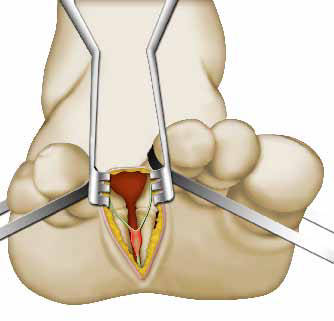

Στη συνέχεια, ανοίγει το δέρμα, κόβει τον ελαστικό ιστό (σύνδεσμο) και παραμερίζει το λίπος, για να φτάσει το νεύρο, που έχει υποστεί βλάβη.

Η τεχνική είναι παρόμοια, σε περίπτωση που η τομή γίνει στο άνω τμήμα του άκρου ποδιού. Ο χειρουργός χρειάζεται, ωστόσο, να απομακρύνει περισσότερα στοιχεία, για να φτάσει το νεύρο (συνδέσμους, αγγεία, νεύρα).

Η βασική επέμβαση

Υπάρχουν δυο τεχνικές για την αντιμετώπιση του συμπιεσμένου νεύρου. Ο χειρουργός σας επιλέγει ανάλογα με την κατάστασή σας και τις μεθόδους που εφαρμόζει. Μη διστάσετε να συζητήσετε μαζί του.

Ο γιατρός σας μπορεί να κόψει το νεύρο (εκτομή). Συνήθως, η τομή πραγματοποιείται στις μαλακές δομές (π.χ. λίπος), για να αποτραπούν οι επίμονοι πόνοι μετά την επέμβαση.

Μην ανησυχείτε, καθώς η εκτομή πραγματοποιείται σε αισθητικό νεύρο και όχι σε νεύρο, που συμβάλλει στην κίνηση των δακτύλων (κινητικό νεύρο).

Η κίνηση των δακτύλων γίνεται φυσιολογικά, αλλά χάνεται μέρος της αισθητικότητας του εγχειρισμένου δακτύλου.

Η δεύτερη τεχνική αφορά στην απελευθέρωση του νεύρου, χωρίς εκτομή (νευρόλυση). Σε αυτή την περίπτωση, ο χειρουργός απελευθερώνει το νεύρο από τα στοιχεία που το συμπιέζουν. Συνήθως, ο χειρουργός επιλέγει να κόψει το νεύρο (εκτομή), παρά την απελευθέρωσή του (νευρόλυση), για να αποφύγει την επανεμφάνιση του προβλήματος.